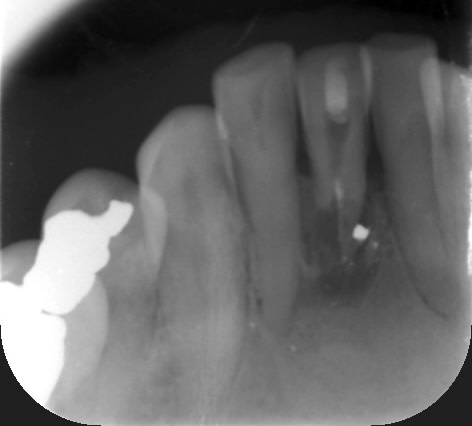

tu veux la radio ? , ben la voilà